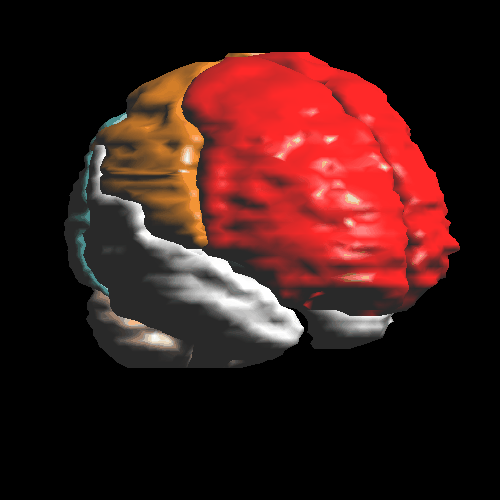

The image shows all Brodmann areas outlined in a PET-slice (left), and the identification

of a single gyrus in an MR-slice using the point-and-click method (right).